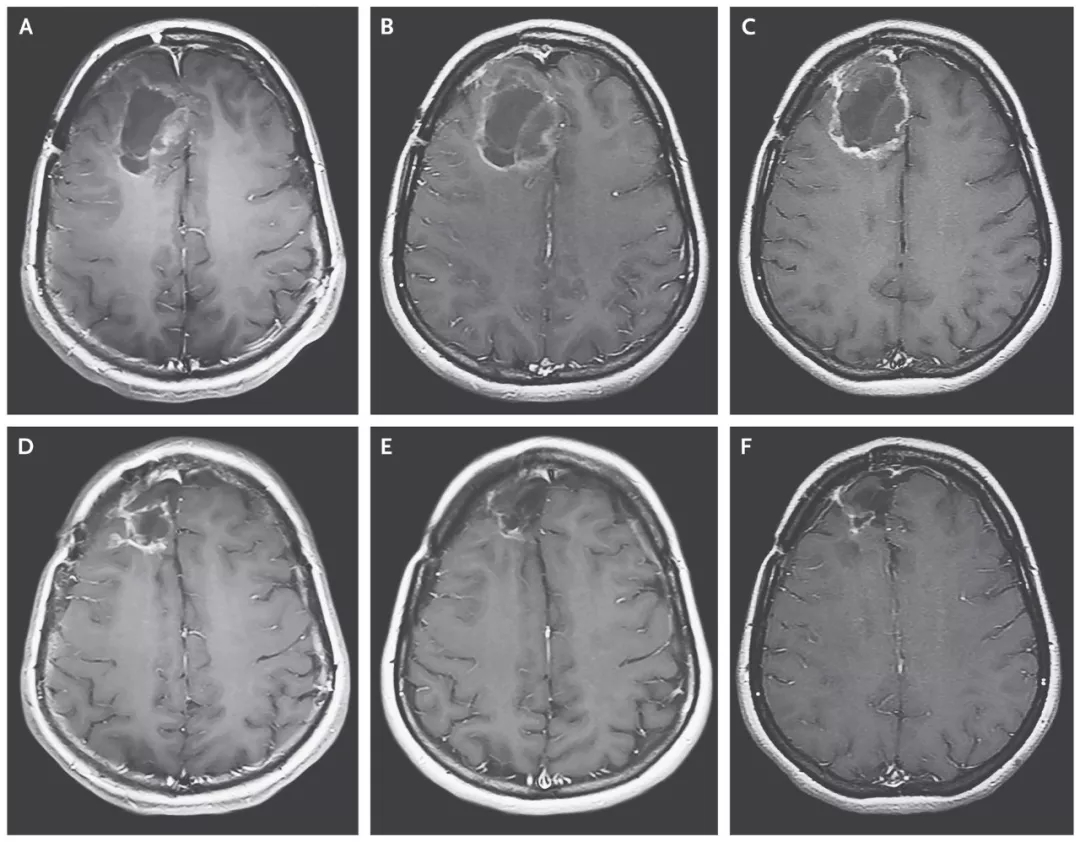

(患者脑部肿瘤的缩小清晰可见)

20岁多岁的斯蒂芬妮·利普斯科姆是一名脑胶质母细胞瘤复发患者,被医生断言仅剩几个月的生命。幸运的是,她成为了首名接受这项试验性病毒治疗的患者。在接受治疗后,她大脑里的肿瘤不断缩小。在2014年,肿瘤竟彻底消失了。这个“奇迹”经美国CBS电视台知名栏目《60分钟》报道后,震惊全美。